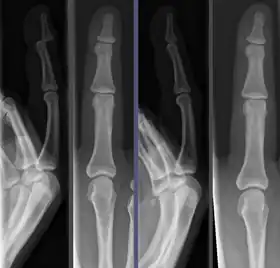

![]() Joint dislocation in the DIP of the third finger before (left images) and after (right images) reduction. | |

Once the fragments are reduced, the reduction is maintained by application of casts, traction, or held by plates, screws, or other implants, which may in turn be external or internal. It is very important to verify the accuracy of reduction by clinical tests and X-ray, especially in the case of joint dislocations.